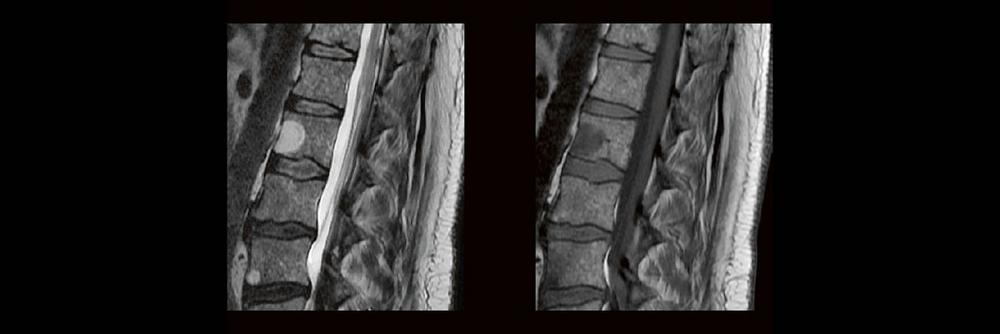

In der täglichen Routine hat man wenig Zeit, sich lange mit den Bildern zu beschäftigen, die man anfertigt. Dennoch soll man auf bestimmte Erkrankungen richtig reagieren und die Protokolle anpassen. MTR´s sind keine Ärzte, dennoch gibt es ein Krankheiten, die eindeutige Bildmerkmale zeigen. In diesem Webinar werden eine Reihe solche Erkrankungen gezeigt. Woran erkennt man einen Schlaganfall, ein Hämagiom, eine Metastase oder Fraktur? Diagnosen die man sehen muss um richtig zu reagieren? – hier werden sie gezeigt.